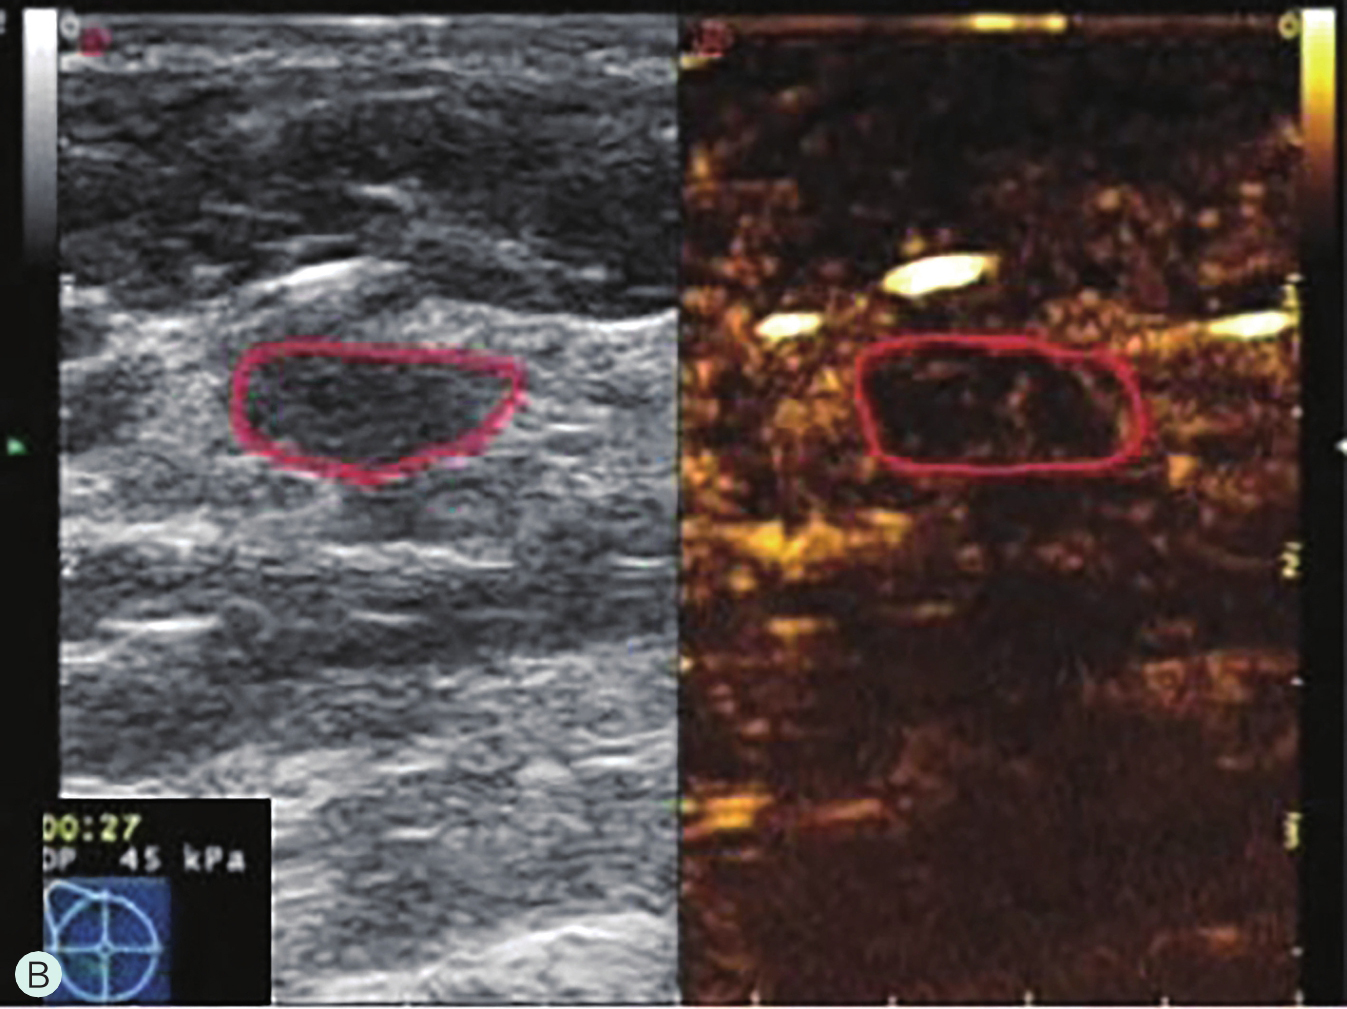

图2-2-8 分析与判读

A.同步测量病灶大小与高增强范围;B.勾勒病灶与增强范围;C.定量分析